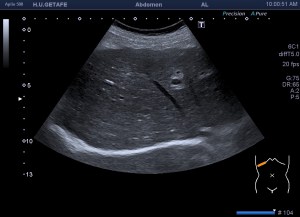

- Vesícula biliar: Visualizada como una estructura en forma de pera, que puede variar en tamaño según la cantidad de bilis que contenga. Su pared aparece como una línea hiperecogénica y suele tener un grosor menor a 3 mm.

- Lumen: Es la cavidad interna de la vesícula biliar donde se almacena la bilis. Se visualiza como una zona anecoica (sin ecos) rodeada por la pared hiperecogénica.